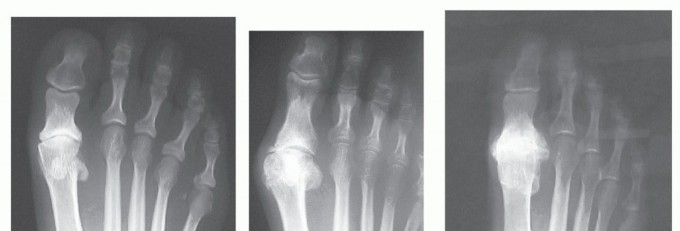

Implant is retained and conversion to total toe arthroplasty by placing matching proximal phalangeal metal component with polyethylene insert. If first-generation design, will need to exchange to HemiCAP DF to match the phalangeal and polyethylene component (FIG 11).

Implant removal and conversion to first MTP arthrodesis (FIG 12). Have freeze-dried allograft femoral head or iliac crest available. The author has had excellent results with intercalary allograft in the few instances where patients desired the implant to be removed due to pain. After implant removal and adequately preparing the joint, the approximate bone gap measured 2.0 to 2.5 cm. We have simply used a structural allograft (freeze-dried femoral head or iliac crest) cut to size and contoured using convex/concave reamer system to maintain hallux length on implant removal. In our experience, this has not been a complex procedure yet requires the appropriate graft and equipment for the case to flow smoothly.

FIG 12 • A. Patient developed arthrofibrosis and persistent pain despite proper implant alignment and no evidence of loosening. Elected for implant removal and conversion to fusion. B,C. Implant removed and intercalary allograft placed to maintain hallux length. Freeze-dried femoral head allograft used. Prepared with convex/concave reamers and stabilized with dorsal plate fixation. Solid bone fusion noted on AP and lateral radiographs. Weil osteotomy performed on second metatarsal and proximal interphalangeal (PIP) arthrodesis to address lateral transfer metatarsalgia and semirigid hammer toe deformity.